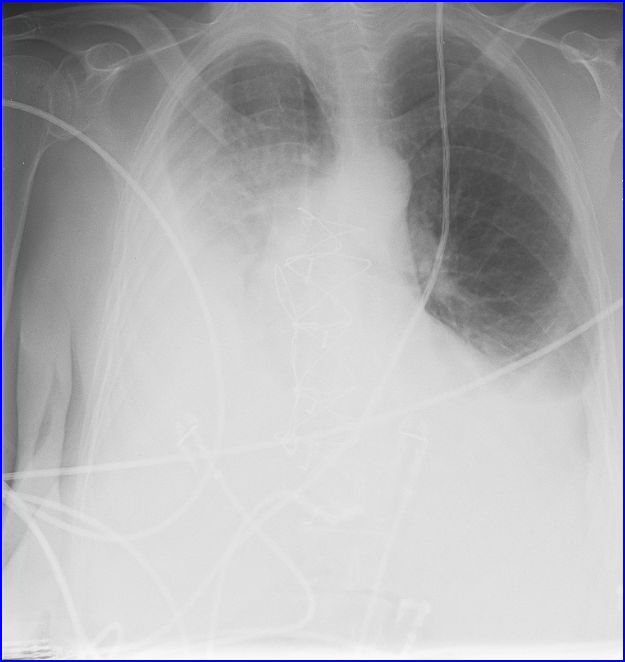

What Causes White Out On Chest X Ray . These three causes are extensive pneumonia, collapse. Within one week, alveolar pulmonary edema (hyaline. The differential diagnosis can be shortened further with one simple observation: Frontal radiograph of the chest reveals complete opacification of the left hemithorax with deviation of the trachea to the left. Collapse (atelectasis) of an entire lung; This patient had a chronic disease with progressive consolidation. The radiologist who interprets the x. Unilateral opaque (“white out”) hemithorax: A white spot amidst the normal black lungs can therefore be a cancer, infection, bleeding, fluid, foreign body amongst other possibilities.

What Causes White Out On Chest X Ray Frontal radiograph of the chest reveals complete opacification of the left hemithorax with deviation of the trachea to the left. The differential diagnosis can be shortened further with one simple observation: Frontal radiograph of the chest reveals complete opacification of the left hemithorax with deviation of the trachea to the left. This patient had a chronic disease with progressive consolidation. Within one week, alveolar pulmonary edema (hyaline. Collapse (atelectasis) of an entire lung; These three causes are extensive pneumonia, collapse. The radiologist who interprets the x. Unilateral opaque (“white out”) hemithorax: A white spot amidst the normal black lungs can therefore be a cancer, infection, bleeding, fluid, foreign body amongst other possibilities.

Med 5 Talk Chest 1 CXR Unilateral 'whiteout' with posit… Flickr What Causes White Out On Chest X Ray Frontal radiograph of the chest reveals complete opacification of the left hemithorax with deviation of the trachea to the left. Collapse (atelectasis) of an entire lung; This patient had a chronic disease with progressive consolidation. These three causes are extensive pneumonia, collapse. The differential diagnosis can be shortened further with one simple observation: A white spot amidst the normal black. What Causes White Out On Chest X Ray.